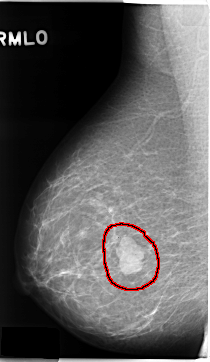

C_0131_1.RIGHT_MLO

RIGHT_MLO LINES 4704 PIXELS_PER_LINE 2720 BITS_PER_PIXEL 12 RESOLUTION 50 OVERLAY

FILE: C_0131_1.RIGHT_MLO.OVERLAY

TOTAL_ABNORMALITIES 1

ABNORMALITY 1

LESION_TYPE MASS SHAPE LOBULATED MARGINS CIRCUMSCRIBED

ASSESSMENT 5

SUBTLETY 5

PATHOLOGY MALIGNANT

TOTAL_OUTLINES 1

BOUNDARY